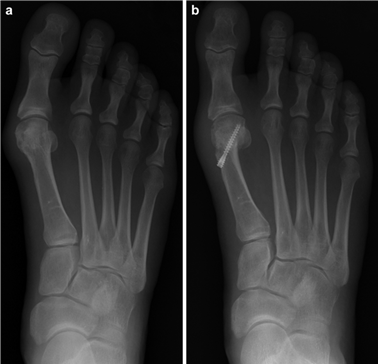

When conservative measures fail, the choice of procedure is dictated by the severity of the deformity, the presence of degenerative joint disease, and the stability of the first TMT joint. Distal osteotomies (e.g., Chevron) are generally reserved for mild to moderate deformities with an intermetatarsal angle (IMA) less than 13 degrees. Diaphyseal osteotomies (e.g., Scarf) offer greater translational correction for moderate to severe deformities. Proximal procedures, such as the Lapidus arthrodesis, are indicated for severe deformities (IMA > 15 degrees), clinical hypermobility of the first TMT joint, or recurrent hallux valgus. For hallux rigidus, joint-sparing procedures like cheilectomy are indicated for early-stage disease, while first MTP arthrodesis remains the gold standard for end-stage arthritis.

The Modified Chevron Osteotomy

The modified distal Chevron osteotomy is a powerful tool for mild to moderate hallux valgus. A medial longitudinal incision is made centered over the first MTP joint. Dissection is carried down to the joint capsule, taking care to protect the dorsal medial cutaneous nerve. A midline or L-shaped capsulotomy is performed, exposing the medial eminence. The medial eminence is resected parallel to the medial border of the foot, preserving the sagittal groove to avoid disrupting the articular surface.

A V-shaped osteotomy is then created in the metatarsal neck with an apex angle of approximately 60 degrees. The apex is positioned centrally within the metatarsal head, and the limbs exit dorsally and plantarly. The capital fragment is translated laterally by 30-50% of the metatarsal shaft width. If the DMAA is increased, a medial closing wedge can be incorporated into the osteotomy. The osteotomy is provisionally stabilized with a Kirschner wire, and definitive fixation is achieved using one or two headless compression screws directed from dorsal-proximal to plantar-distal. The medial capsule is then imbricated to correct the soft-tissue imbalance, and the skin is closed in layers.

The seminal work by Mann and Coughlin in the late 20th century established the foundational understanding of the pathophysiology of hallux valgus and the critical importance of the intermetatarsal angle in dictating surgical decision-making. Their long-term follow-up studies on the Chevron osteotomy validated its efficacy for mild to moderate deformities, demonstrating high patient satisfaction and low recurrence rates when indications were strictly adhered to.